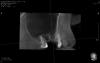

red_butler Опубликовано 1 февраля, 2013 Автор Поделиться Опубликовано 1 февраля, 2013 Выкладываю кт до. В первую очередь интересует состояние слизистой, и как туды винты теперь ставить. И конечно вопрос ПОЧЕМУ, хотя причинно-следственная связь вполне очевидна. Забыл написать - синус был двух-сторонний и слева все o`k Ссылка на комментарий

777white Опубликовано 12 февраля, 2013 Поделиться Опубликовано 12 февраля, 2013 Выкладываю кт до. В первую очередь интересует состояние слизистой, и как туды винты теперь ставить. И конечно вопрос ПОЧЕМУ, хотя причинно-следственная связь вполне очевидна. Забыл написать - синус был двух-сторонний и слева все o`kПо к/т уже до операции слизистая утолщена была, то есть воспалена. ИмхоЯ за то что там инфицированный графт как каша, кости там нет... Чистить надоЖдем Лора Ссылка на комментарий

kriokov Опубликовано 12 февраля, 2013 Поделиться Опубликовано 12 февраля, 2013 (изменено) про затеки не совсем понял. То что отслаивать пошире и поглубже согласен, а так графта получилось не густо, не во всей " бухте" графт. И неполная септа там похоже до. Изменено 12 февраля, 2013 пользователем kriokov Ссылка на комментарий

red_butler Опубликовано 13 февраля, 2013 Автор Поделиться Опубликовано 13 февраля, 2013 ОРВИ было с месяц назад, но левый синус без патологии. Согласен что графта пожалел, хотя отслаивался до небной стенки - но что есть то уже есть. Септа была- доступ двумя окнами. В общем жду что лор скажет и полезу. 1 Ссылка на комментарий